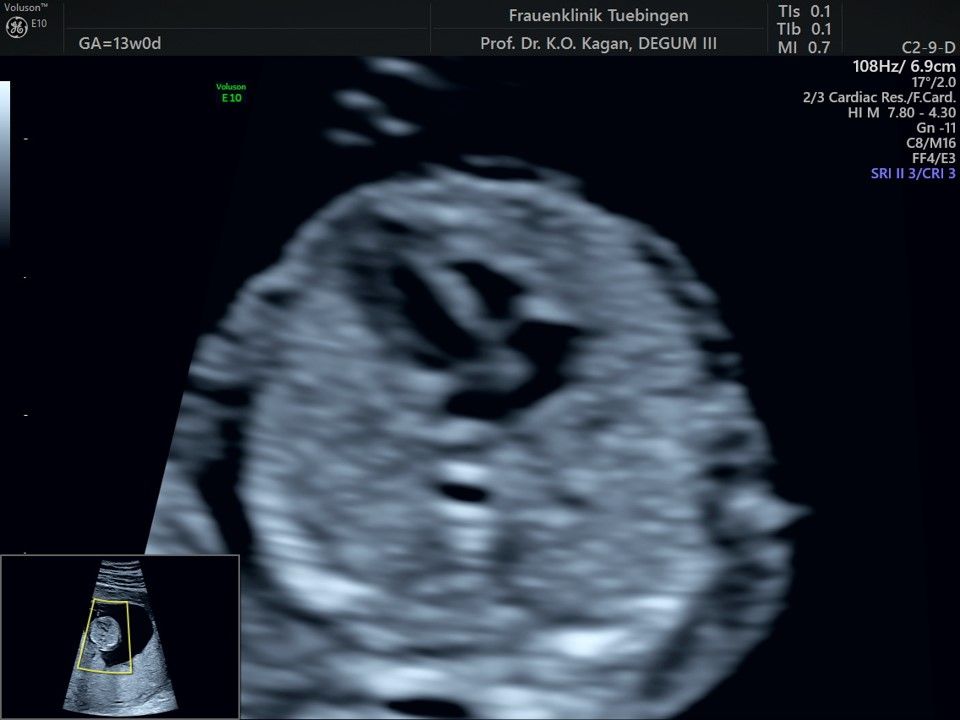

Herz

Das Ergebnis der Ultraschalluntersuchung ist wegweisend. Dabei wird der Fet vermessen, die Organe werden untersucht und die sonographischen Marker zur Risikoberechnung für Chromosomenstörungen werden beurteilt. Das sind: die Nackentransparenzdicke, Nasenbein sowie der Blutfluss in der rechten Herzhälfte und im Ductus venosus, einem Gefäß in der Leber des Feten.